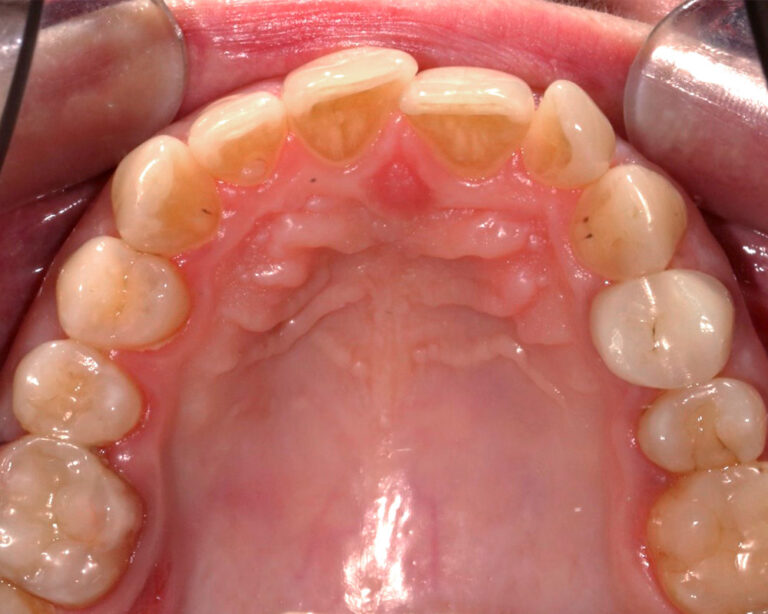

Кейс 21

Количество кап ВЧ 32

Количество кап НЧ 32

ДО

ПОСЛЕ